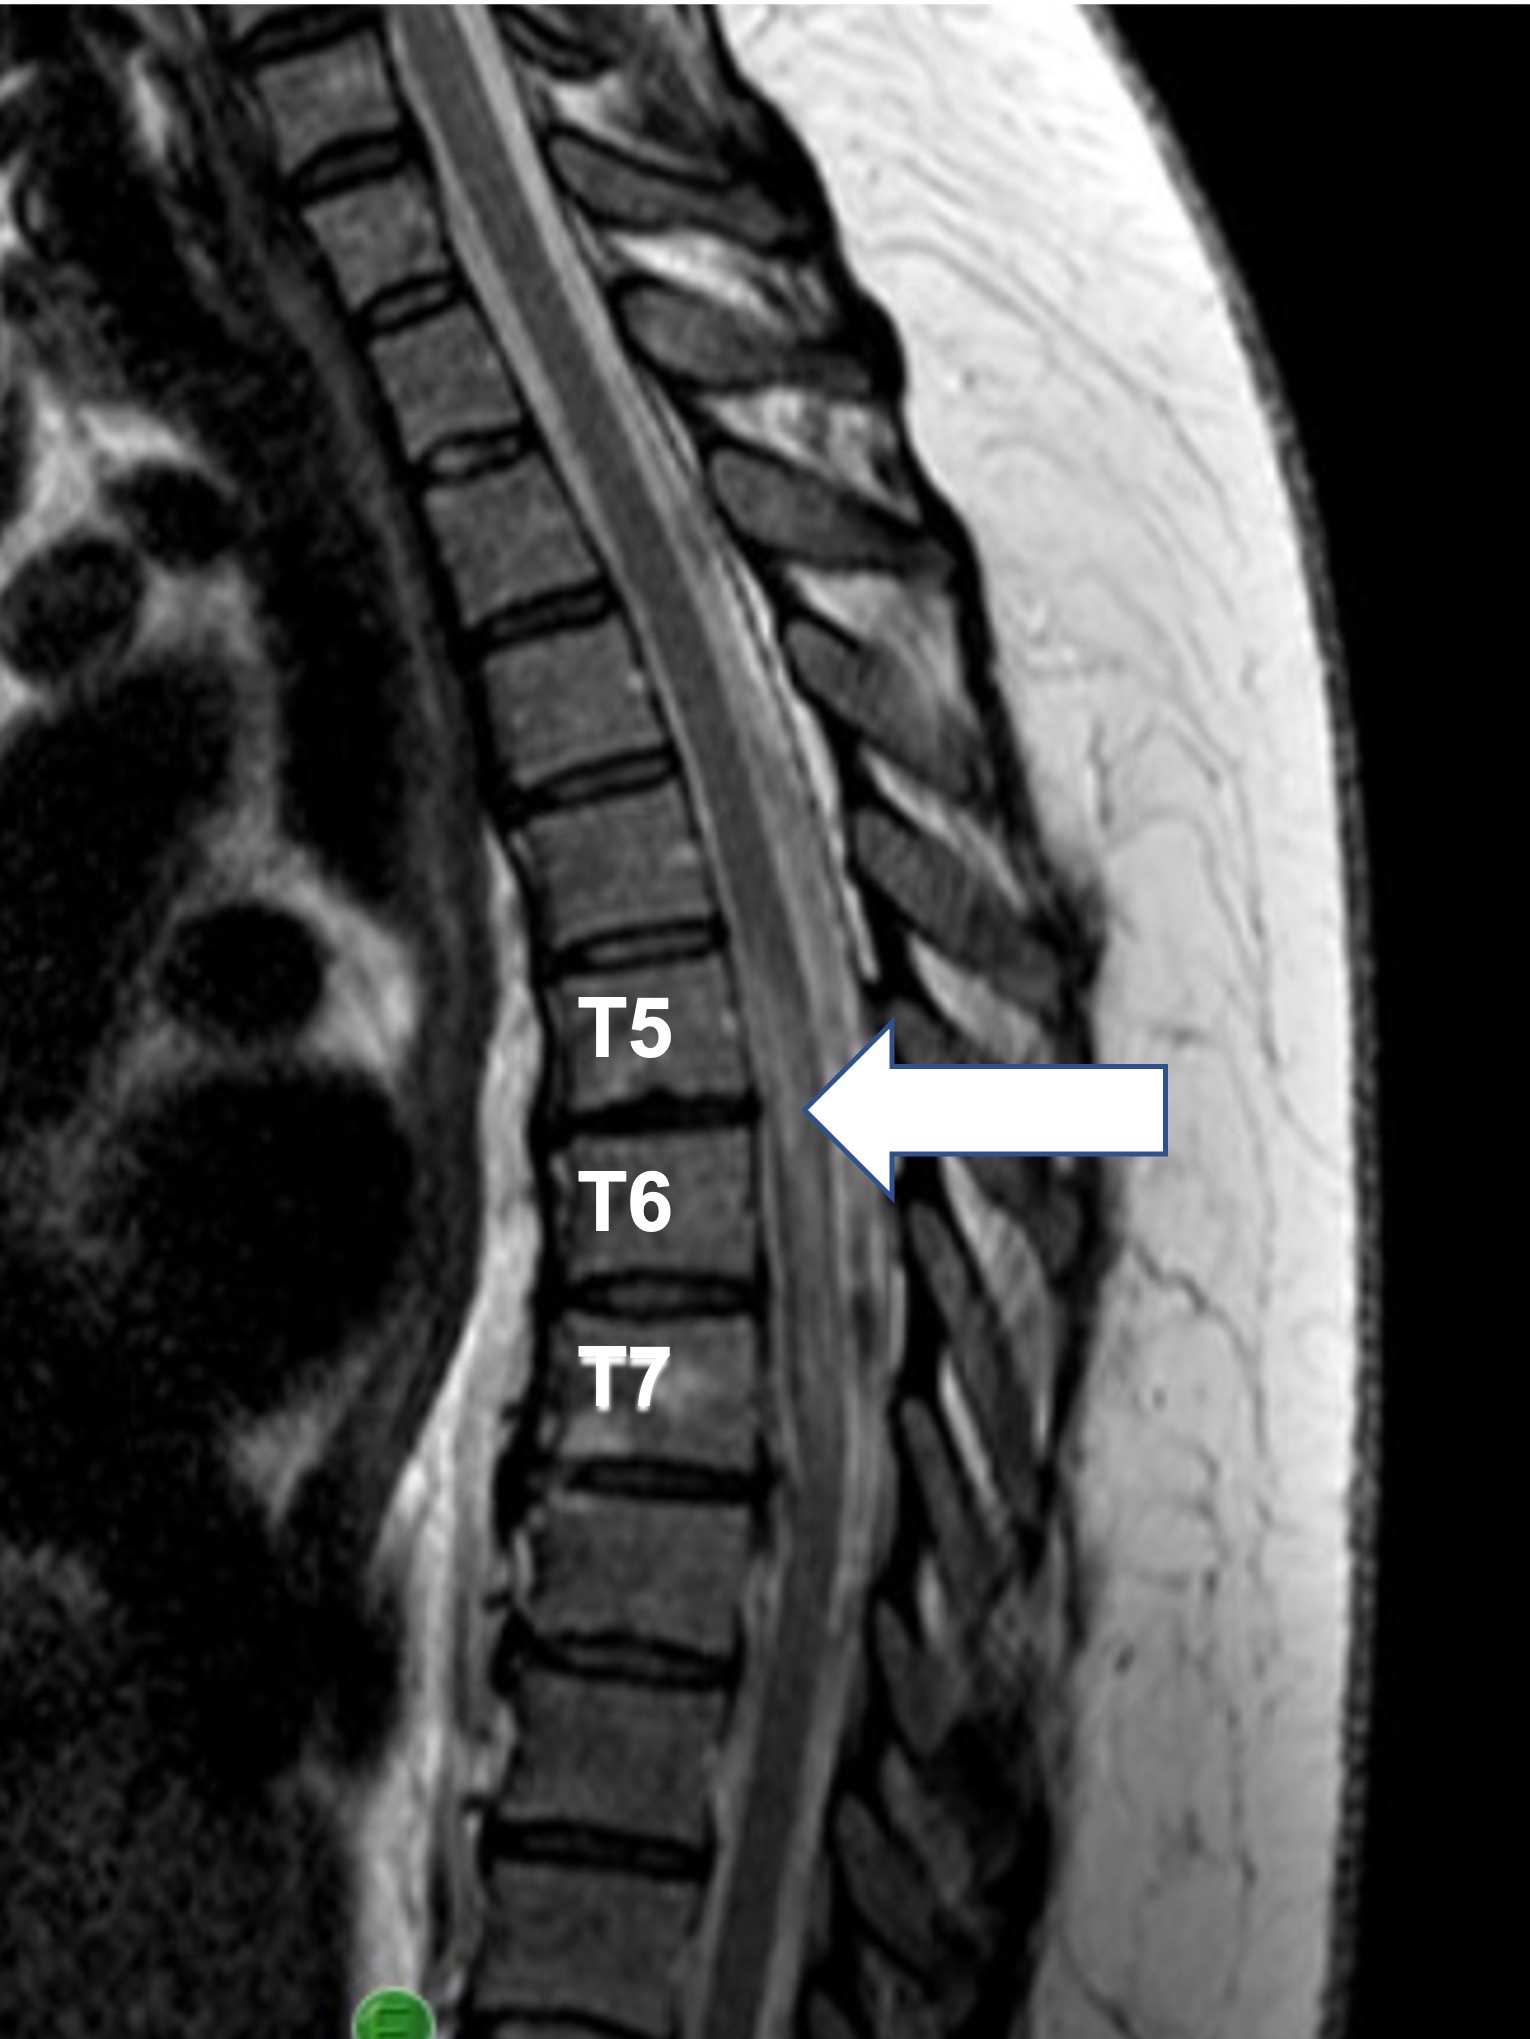

Her initial MRI one day after presentation was unremarkable, but on the following day, imaging demonstrated T2 hyperintensity from T5-7 (Figure 1). She was given 5 days of IV methylprednisolone but not intravenous immunoglobulin or plasmapheresis. At the time of acute care discharge, her diagnosis was not fully determined, with the differential being spinal cord infarct versus a demyelinating disease other than multiple sclerosis (MS) or neuromyelitis optica (NMO). Although ultimately the cause was identified as a spinal cord infarct, the debate in diagnosis caused delayed initiation of comprehensive SCI rehabilitation, occurring approximately 18 days following the onset of paraplegia.

Figure 1. An acute T2 intramedullary signal hyperintensity is seen T5-T7, consistent with spinal cord infarct vs demyelinating disease. Clinical presentation and laboratory findings strongly suggested a diagnosis of infarct over demyelinating disease.